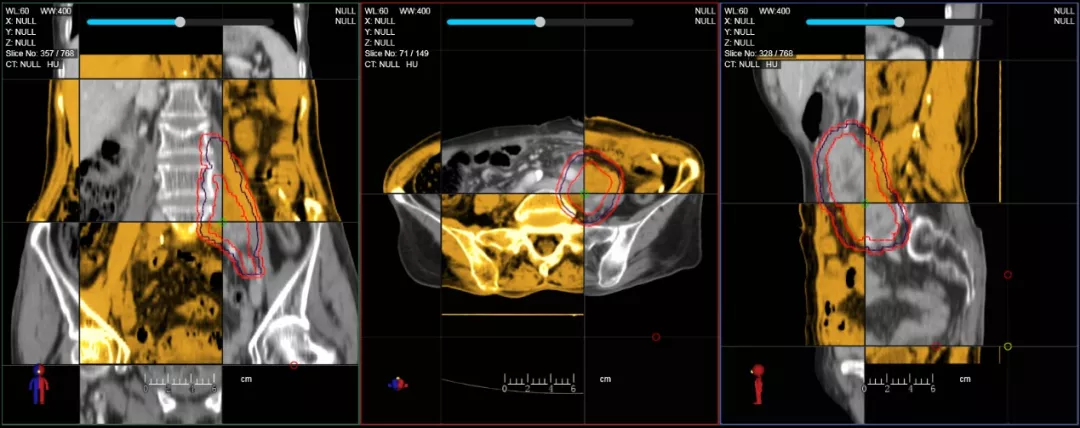

CT-IGRT配準(zhǔn),除骨性標(biāo)記外,還能以器官、軟組織等作為參考,真正找到配準(zhǔn)目標(biāo)

一體化CT-linac讓自適應(yīng)放療ART概念變?yōu)楝F(xiàn)實(shí)?;颊呷煶虪顟B(tài)監(jiān)控,適時(shí)在線調(diào)整治療計(jì)劃,精準(zhǔn)控制治療劑量,為患者動(dòng)態(tài)定制個(gè)體化治療方案。uAI賦能智能勾畫(huà)和自動(dòng)計(jì)劃,秒級(jí)勾勒靶區(qū)和危及器官,大幅縮短自適應(yīng)放療時(shí)間。

在線自適應(yīng)放療流程示意圖